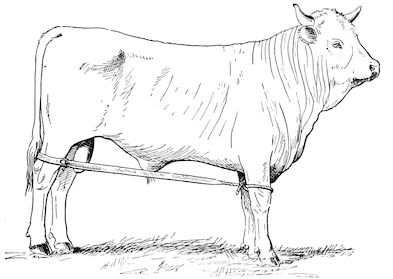

Fig. 1.—Rachitis in a young goat.

Rachitis is a disease of youth, and is common both to the human species and to all domestic animals. It is characterised by irregularities in development and by imperfect consolidation of the bones. The boundary between rachitis and osseous cachexia is difficult to define and in fact at the present moment the two diseases can scarcely be defined with exactitude. Rachitis again is often complicated with softening of the bones, disease of the limbs, arrested development, etc., but it must not be forgotten that although the irregularities in ossification and development of the skeleton are the symptoms most striking to the eye, they do not stand alone, and that from the point of view of development all the tissues, including the muscles, are more or less affected and that most of the physiological functions such as digestion and the secretion of urine are deranged.

Symptoms. The onset is absolutely insidious and the diagnosis of rachitis is never made until nutrition has long been abnormal.

This disturbance of nutrition is revealed by irregularity and abnormality in appetite, by difficulty in rising and moving about, and by the animals lying down for long periods. The subjects are feeble, sluggish and badly developed.

Next supervenes the second phase characterised by deformity of bones. This is of two kinds—deformity in the neighbourhood of joints (deformity or enlargement of the epiphyses) and deformity of the diaphyses. The former results from irregularity in ossification of the articular cartilages. The latter is followed by loss of rigidity in the bones of the limbs which, under the influence of the body weight and of muscular contraction, bend in different directions.

The bones appear of increased thickness principally towards the 6articulations. The latter are deformed, and on palpation are found to be surrounded by uneven and irregular growths.

The front limbs are distorted. In young pigs, lambs, and less frequently in foals, calves and dogs, the jaws become deformed, and mastication is rendered difficult.

The vertebral column may also be affected, and lordosis (bending downwards of the back) or skoliosis (lateral bending of the back) is somewhat frequent.

General development is always interfered with and the young creatures are generally dwarfed.